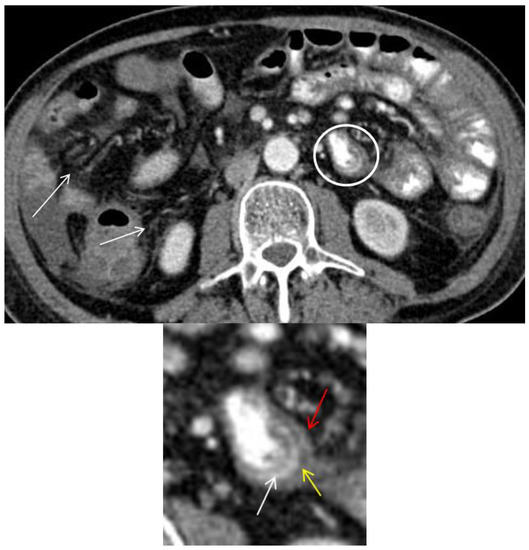

Axial CT image shows circumferential small bowel wall thickening (>3 mm) with trilaminar mural stratification in the small-bowel (circle and magnified image) with serosal enhancement (red arrow), low intramural attenuation (yellow arrow) and mucosal enhancement (white arrow) [2,13]. Low intramural attenuation can represent edema, inflammatory infiltrate or fat [13]. Stranding of the mesenteric fat is often observed in GIT-GVHD [2,6] (arrows). Mural stratification is a non-specific sign of bowel inflammation and has been shown to correlate with clinically active disease as opposed of a more homogenously enhancement due to fibrosis [14,15]. In this patient, three different patterns of mural stratification and mural enhancement were present in separate segments (Figure 2 and Figure 3).